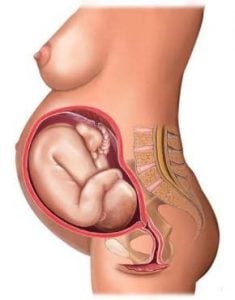

- Desenvolvimento O bebê já possui as feições com que irá nascer e já tem pouco espaço para se movimentar.

- Com 35 semanas de gestação, o bebê mexe muito e a vitalidade do desenvolvimento fetal é impressionante. Os movimentos vigorosos podem surpreender nessa fase.

- Nesta semana o bebê já está com as feições exatas com que nascerá. Todos seus órgãos já estão em perfeito funcionamento, exceto seus pulmões que estão em processo de amadurecimento.

Com 35 semanas de gestação, o bebê mexe muito e a vitalidade do desenvolvimento fetal é impressionante. Os movimentos vigorosos podem surpreender nessa fase. As famosas ondulações fazem com que a gravidez seja ainda mais impressionante para os papais de primeira viagem.

Com 35 semanas o desenvolvimento fetal está completo. Agora o bebê ganha cerca de 30 gramas por dia,e o acúmulo de gordura é necessário para que o bebê ganhe peso adequadamente. Saiba que o ganho de peso do bebê não é proporcional ao ganho de peso da mamãe.

Na 35ª semana de gravidez, o bebê já tem as feições exatas com que nascerá. Todos seus órgãos já estão em perfeito funcionamento, exceto seus pulmões que estão em processo de amadurecimento. Nessa fase eles estão produzindo líquido, garantindo que não parem de funcionar quando o bebê nascer e começar a respirar1.

O bebê com 35 semanas de gravidez chega a medir em torno de 46,2 centímetros e a pesar 2,383 kg. Está na reta final de seu desenvolvimento e agora ganha peso diariamente. Seus movimentos estão cada vez mais escassos pela falta de espaço no útero. Mas ainda é possível notar movimentos bruscos marcando a barriga, principalmente quando passar um cotovelo ou um pé.

Nesta fase, os rins do bebê já funcionam2 e seu fígado consegue fazer sua função de filtrar as substâncias corretamente. A quantidade de líquido amniótico está diminuindo a cada dia. Isto é resultado da ocupação do bebê dentro do útero, que está ficando cada vez maior. Seu útero cresceu tanto para se adequar ao tamanho do bebê que está 100 vezes maior do que o tamanho normal.